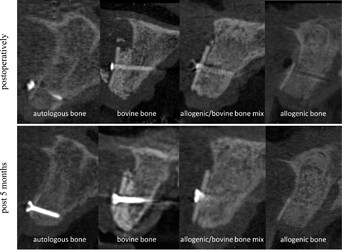

Fig. 7.

Alveolar ridge augmentation with different fillings, autologous bone, bovine substitute, a mixture of allogeneic bone and bovine substitute, and allogeneic bone at CBCT scans. Upper line situation postoperatively and lower line situation after 5 months in CBCT scans